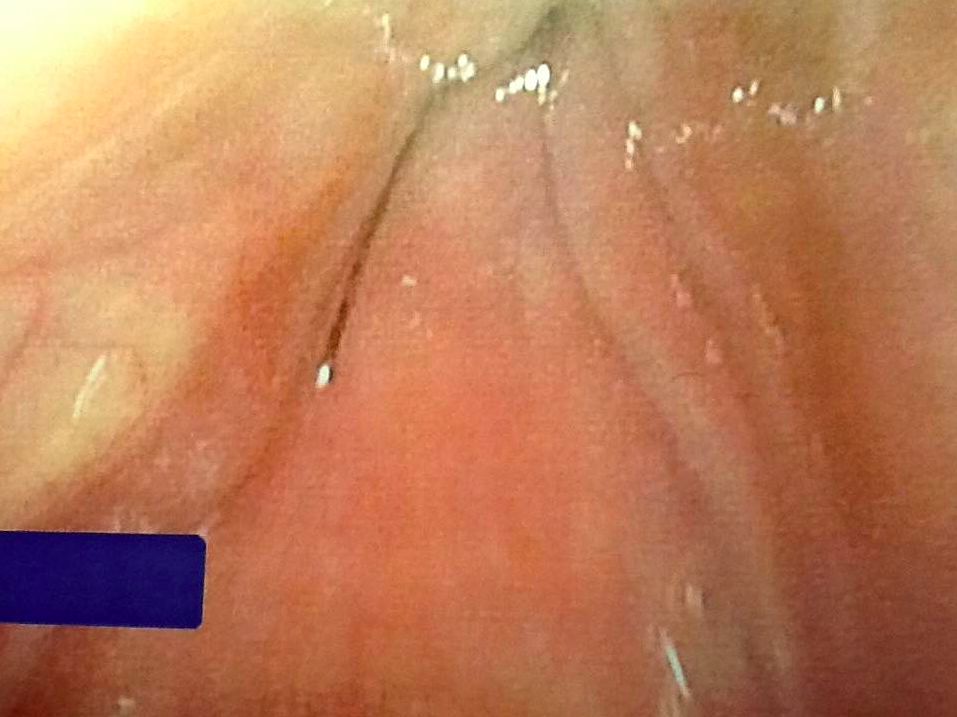

Doctor Finds Grill Brush Lodged in Woman’s Throat for Months Grill Brush Stuck In Throat They're falling off and sticking to grills. By the time ogg saw him in july, the piece of grill brush had migrated from her throat to the side of her neck. The problem is those wire brush bristles. Are wire grill brushes dangerous? Doctor finds grill brush bristle lodged in woman’s throat for months. Using a handheld ultrasound, dr. Meghan. Grill Brush Stuck In Throat.

Grill Brush Stuck In Throat . Using a handheld ultrasound, dr. The problem is those wire brush bristles. And without anyone noticing, they're being picked up by food, and people are eating them. A single hotdog bite landed linda pelham in the hospital unable to breathe, speak or swallow. Meghan martin, a pediatric er doctor, shares a case she saw of a boy who was injured after eating a burger that a piece of a wire from a metal grill brush inside it. Karni located a metallic foreign body on the left side of her neck, lodged in soft tissues near the carotid artery and jugular vein. Expert warns about injuries caused by metal bristles which end up in food and become lodged in the mouth, throat, or intestines. In a tiktok with more than 34 million views, a pediatric emergency room doctor recently shared a story of a boy who was injured by a broken wire from a grill cleaning brush. By the time ogg saw him in july, the piece of grill brush had migrated from her throat to the side of her neck. Meghan martin talks about the hidden dangers of grill brushes after a wire got stuck in a 4. Doctor finds grill brush bristle lodged in woman’s throat for months. Are wire grill brushes dangerous? They're falling off and sticking to grills.